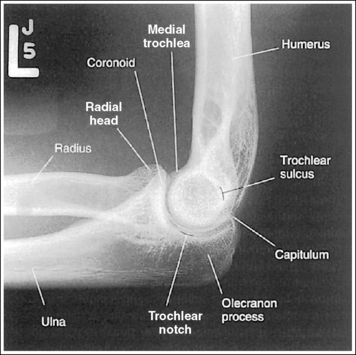

The capitulum-radius joint is either partially or completely closed, and the radial head articulating surface is demonstrated. The olecranon process is situated within the olecranon fossa, and the coronoid process is visible on end.

The distal humerus is in a lateral projection. The distal humerus demonstrates three concentric (having the same center) arcs, formed by the trochlear sulcus, capitulum, and medial aspect of the trochlea. The elbow joint space is open, and the radial head is superimposed over the coronoid process.

The elbow is positioned in an AP projection. The medial and lateral humeral epicondyles are demonstrated in profile at the extreme medial and lateral edges of the distal humerus, and the radial head is superimposed over the lateral aspect of the proximal ulna by approximately 0.25 inch (0.6 cm). The coronoid process is demonstrated on end.

The elbow is in a lateral projection. The distal humerus demonstrates three concentric arcs, which are formed by the trochlear sulcus, capitulum, and medial trochlea. The elbow joint space is open, and the radial head is superimposed over the coronoid process.